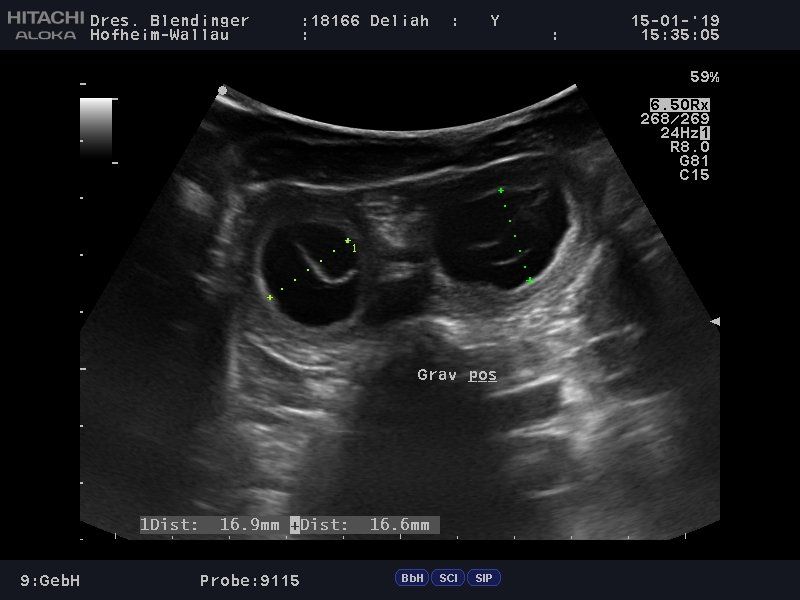

15.01.2019

Was wir die ganze Zeit schon geahnt haben,

hat heute der Ultraschall bestätigt:

Unsere Schnuppe ist trächtig!

Abgabetermin der Welpen wird Mitte April sein.